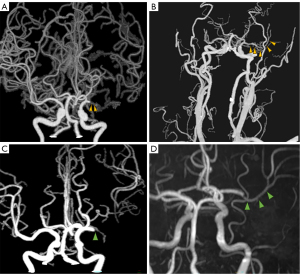

AOL grades 1 and 2 were classified as partial recanalization, while grade 3 was classified as complete recanalization (Figure 1). ESR was considered to include partial recanalization and complete recanalization. Patients were classified into a no-recanalization group if the artery remained occluded and was graded 0 between 7 and 90 days after the initial assessment. Patients were classified into a noncomplete recanalization group if no-recanalization or partial recanalization. All images were independently analyzed by two experienced neuroradiologists. Disagreements were resolved by consensus reading.